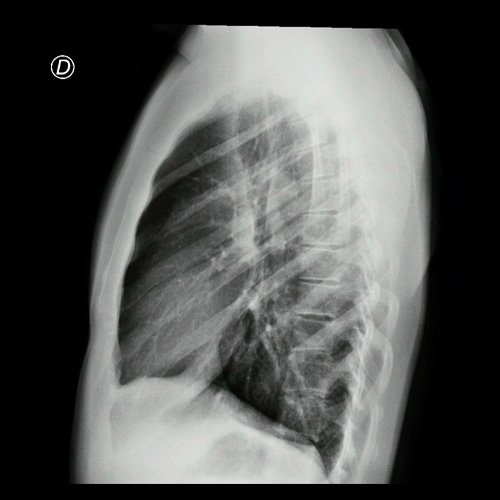

• Radiografía de tórax frente (Día 3): centrada, índice cardiotorácico conservado , senos costofrénicos libres. Sin consolidaciones pleuroparenquimatosas.

Radiografía de tórax frente y perfil  Día 3